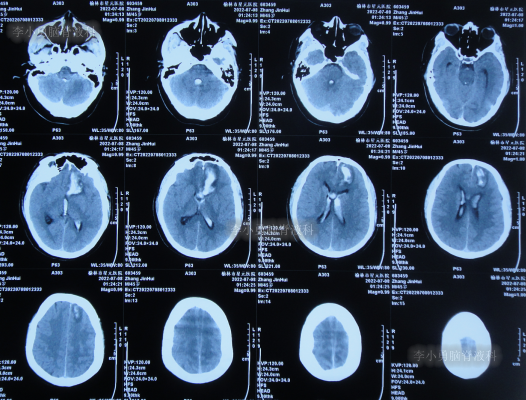

患者于2022年7月8日凌晨突发头痛,伴有胡言乱语,右下肢明显乏力,被家属送至附近的陕西省榆林市某医院,查头颅CT示脑出血(图-1),考虑脑动脉瘤破裂;当即给予了DSA检查发现前交通动脉瘤(图-2)。

图-1:2022年7月8日头颅CT